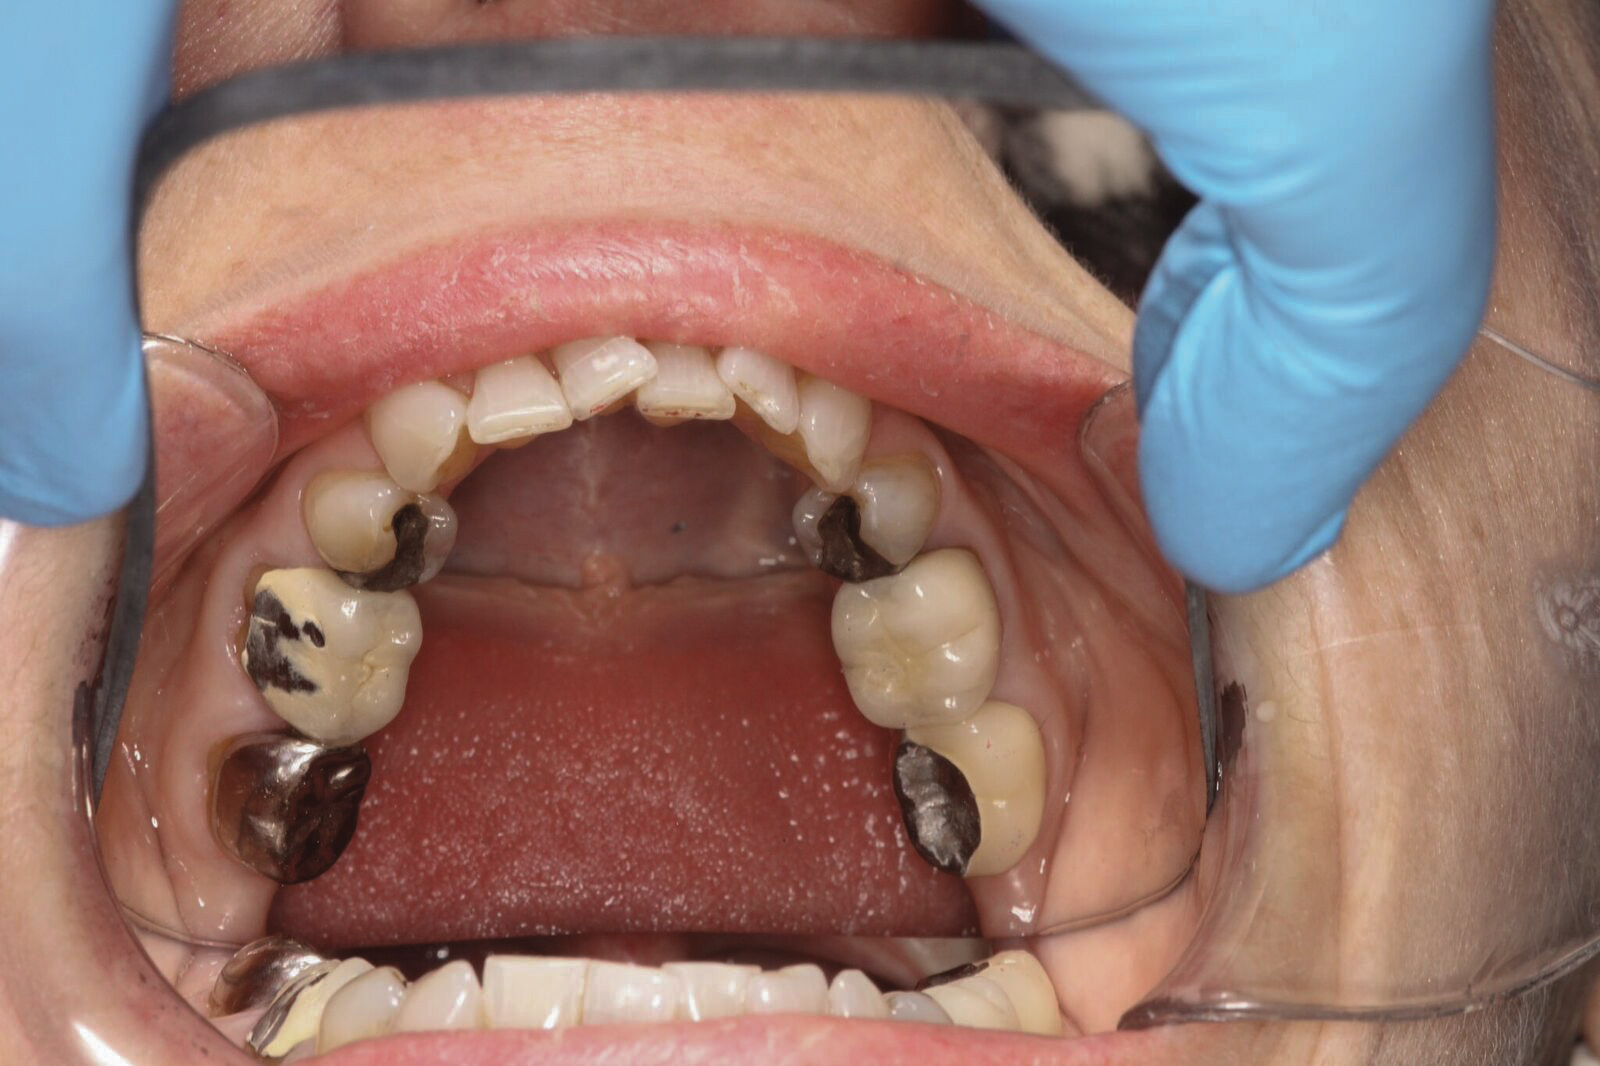

Dental sleep medicine (DSM) is a field in dentistry dedicated to the use and research of oral appliance therapy for the management of snoring and OSA. Oral appliance therapy is a noninvasive alternative to PAP therapy. Oral appliances fabricated by dentists with training in dental sleep medicine are commonly used to reposition the lower jaw forward to increase upper airway patency. Dental professionals have been recognized as being part of the multidisciplinary therapeutic team for the management of OSA because of their prime position of constant examination of the oropharyngeal areas. There are several oropharyngeal features contributing to the development of a narrow upper airway. These features are easily identifiable during a routine dental appointment, such as a large and scalloped tongue (Figure 1), narrow maxilla (Figure 2), small mandible (Figure 3), and retrognathic mandible (Figure 4). Combining clinical history intake, oropharyngeal examination, and the use of validated screening questionnaires, such as the STOP-Bang, dentists can screen for signs and symptoms of OSA and make recommendations for further diagnostic testing.

(1.) Large and scalloped tongue.

Figure 1